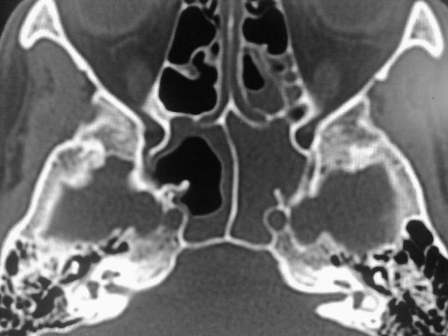

КТ-снимки хронического этмоидита: подробная визуализация

Раздел: Фотодневник открытий